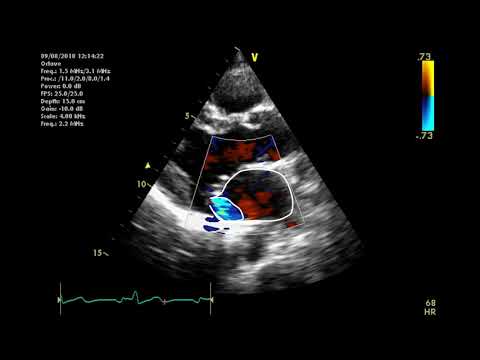

⚠️ Updated Lecture Available! This version of the Mitral Stenosis lecture is from an earlier year. For the new, improved, and fully visual 2025 edition, watch it here: 👉 NEW 2025 Mitral Stenosis Lecture: This original video is still available for reference, but the updated lecture includes: New 2025 echo visuals Updated explanations Clearer Doppler + 2D imaging examples Registry-focused breakdowns Better flow + improved teaching clarity If you're studying for boards or clinicals, I strongly recommend watching the new version. In this cardiac ultrasound tutorial, we break down mitral valve stenosis from an echocardiography perspective. Learn how to identify the key 2D, M-mode, and Doppler findings that confirm mitral stenosis, Whether you’re a cardiac sonography student, RDCS preparing for boards, or an ultrasound professional looking to refine your echo skills, this video provides a clear, step-by-step explanation of what mitral stenosis looks like on echo and how to properly evaluate its severity. Chapters: 📌 Cardiac Ultrasound Topics Covered: • What mitral valve stenosis is and how it affects cardiac function • Classic 2D echo findings (hockey-stick anterior leaflet, thickened leaflets, reduced mobility) • Doppler evaluation: pressure half-time, mean gradients, and diastolic flow patterns • Techniques for optimizing apical and parasternal views • How to differentiate mild, moderate, and severe stenosis on echo • Common pitfalls and how to avoid mis-measurements • Clinical significance and correlation with symptoms 🎯 Perfect for: • Cardiac sonographers • RDCS / CCI exam prep • Echocardiography students • Healthcare professionals learning cardiac imaging 👍 Like, subscribe, and share for more cardiac ultrasound education, echo tips, and pathology breakdowns! #ValvularHeartDisease #Echocardiography #EchoEducation #EchoNotebook #EchoLearning #EchoStudent #EchoTraining #CardiacSonography #SonographyEducation #CardiacUltrasound